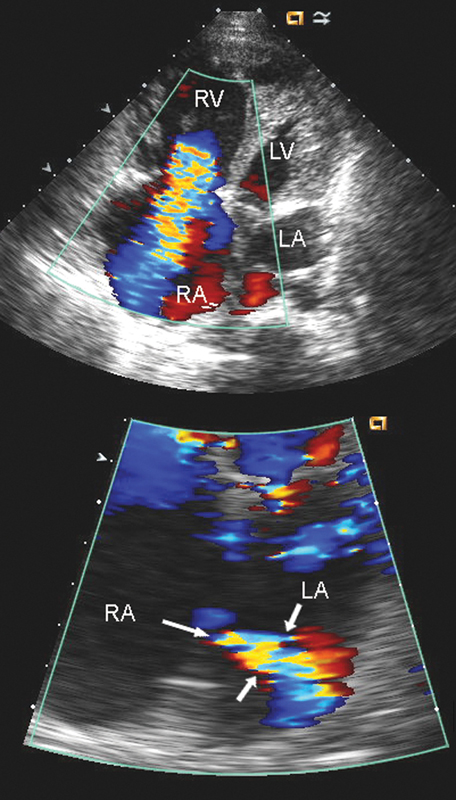

فحوصات تشخيصية لبعض امراض القلب والشرايين التاجية